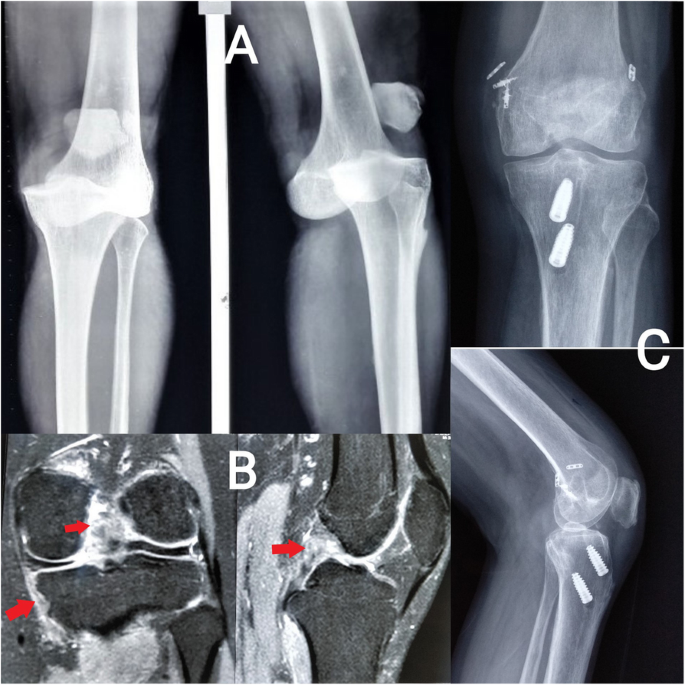

a Fat-suppressed coronal MRI images of a patient with ACL and PCL tears (red arrows show discontinuity of fibres from the femoral attachments). b For patient with a knee dislocation, radiographs before reduction of the knee joint. c For patient with a KD type II injury, postoperative radiograph after ACL and PCL reconstruction